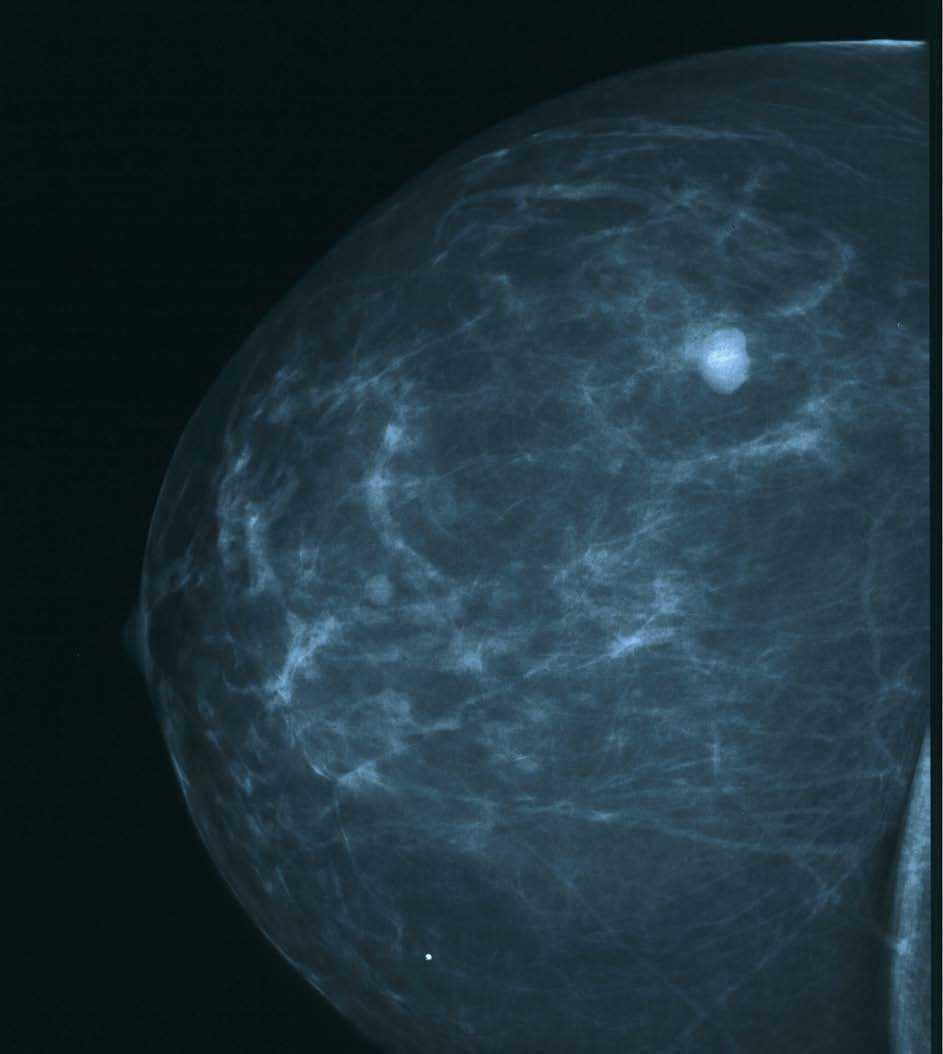

En una mamografía de control, realizada en marzo de 2004, se visualizó en los intercuadrantes superiores de la mama izquierda, hacia el cuadrante superoexterno, una lesión nodular con bordes espiculados y alguna probable microcalcificación en el interior (figs. 1 y 2). En la ecografía se confirma la presencia de una lesión sólida, hipoecogénica, que no produce amortiguación del sonido, compatible con un proceso neoformativo; en la axila se distingue una adenopatía de 1,3-2,3 cm, de aspecto inflamatorio residual.

Figura 1. Mamografía izquierda. Lesión nodular.

Figura 2. Mamografía izquierda. Lesión nodular.